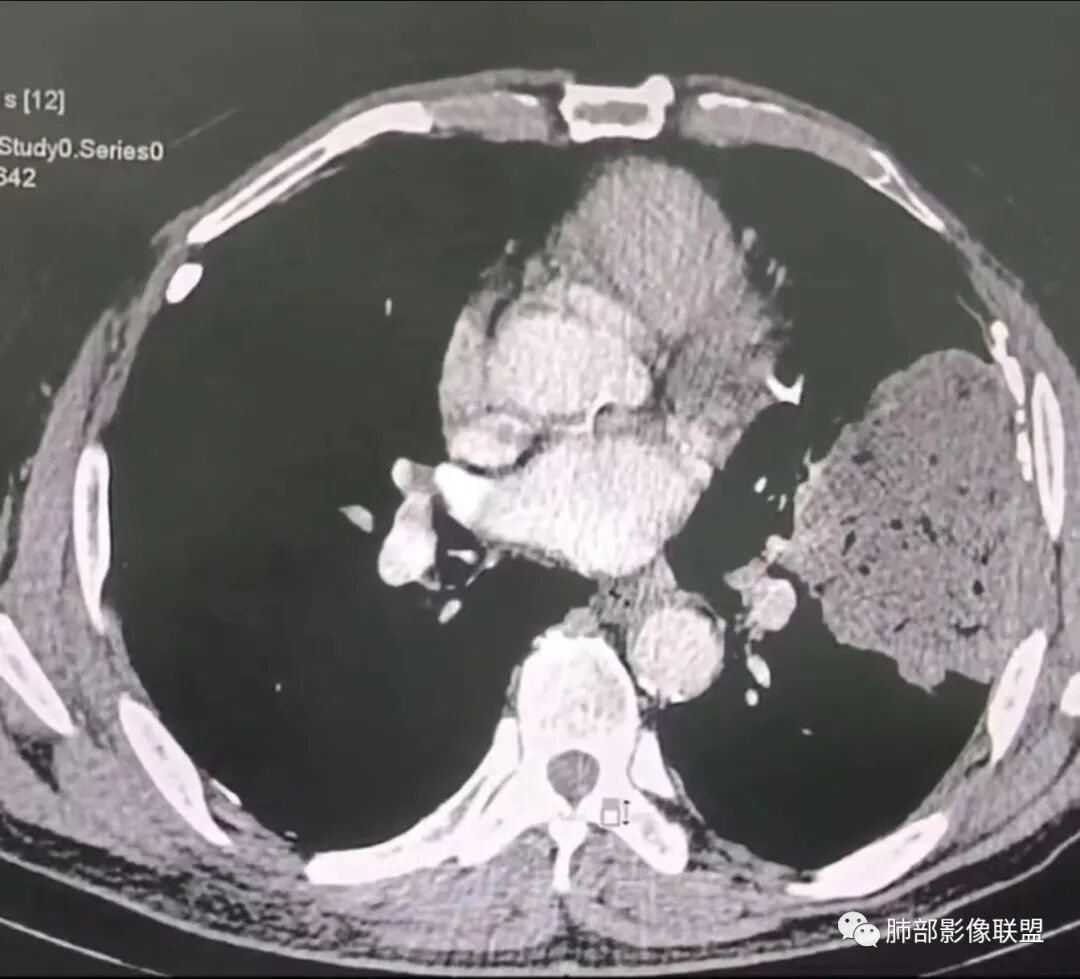

我要修正一下观点了:仔细看了视频,肿块占位效应明显,对周围血管,支气管有推挤,增强后强化不明显,NSE增高,半年体重下降25公斤,虽然有内部支气管扩张,血管漂浮,边界清楚支持淋巴瘤,但强化太低,膨隆,占位推挤太明显(淋巴瘤一般没有这么明显的占位效应),胸膜关系有载桩,恶病质明显(乏力,半年体重下降了25公斤),NSE也明显增高,就不支持淋巴瘤了。还是考虑外朝内的恶性肿瘤,间质来源的肉瘤伴有神经内分泌分化或者大神泌。

不支持淋巴瘤的有四点:1、对周围血管支气管推挤明显。2、胸膜有栽桩,3、强化太弱(淋巴瘤一般还是中度以上甚至高度强化多见),4、NSE升高明显,体重下降太明显。

腺癌一般不会有这么明显的推挤作用的。

我再建一下血管。支气管进入,但是近端推移,堵塞

大肿块,边缘光滑,深分叶

近端支气管堵塞、推移为主

部分类似于脐凹征

内部支气管扩张

肺动脉推移为主,边缘部分进入